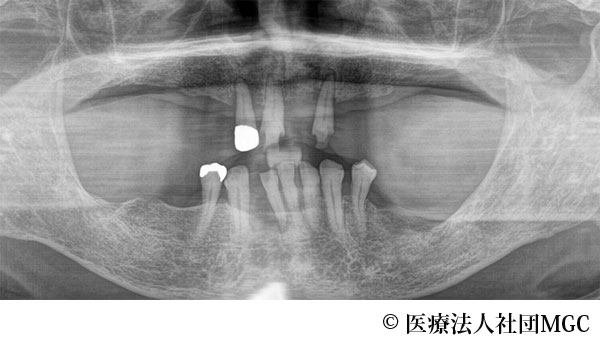

【症例1】上下All-on-4(オールオンフォー)

- 治療前

- 治療名

- 上下All-on-4(オールオンフォー)

- 費用

- 5,915,800円(税込)

- 期間

- 8ヵ月

治療内容

患者様の症状

歯がボロボロで食事が困難であるとご来院されました。

治療法

ご相談の結果、患者様の生活の質(QOL)を向上させ、しっかり噛めるように上下All-on-4(オールオンフォー)を行いました。

治療結果

機能性、審美性ともに改善し、満足していただけました。

※治療結果は患者様によって個人差があります。

治療を行う上での注意点(リスク・副作用)

インプラント周囲炎の可能性、まれに歯が欠ける可能性があります。